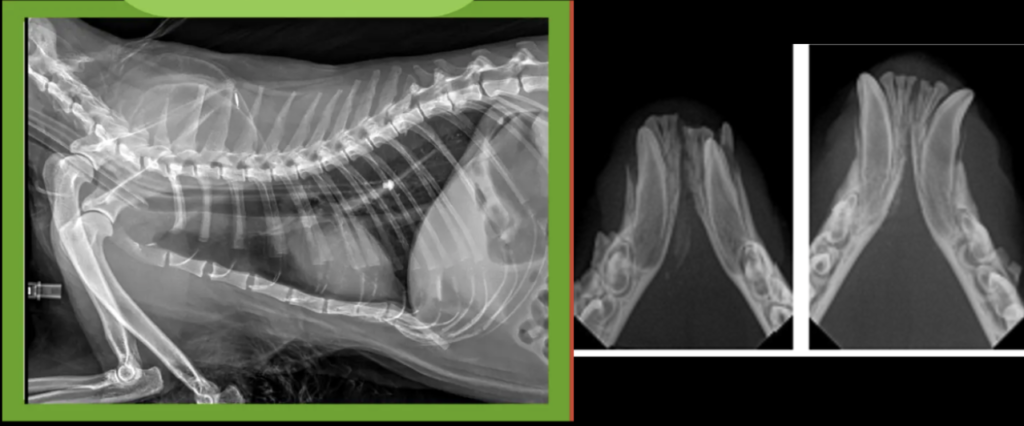

However, in TBI patients, hypertonic saline and mannitol can complicate CDI diagnosis. Since Boris’ hypernatremia resolved within 36-48 hours without DDAVP, we can only speculate whether transient CDI contributed.

Figure 2. The lack of ADH secretion secondary to TBI may lead to profound polyuria leading to free water loss and hypernatremia.